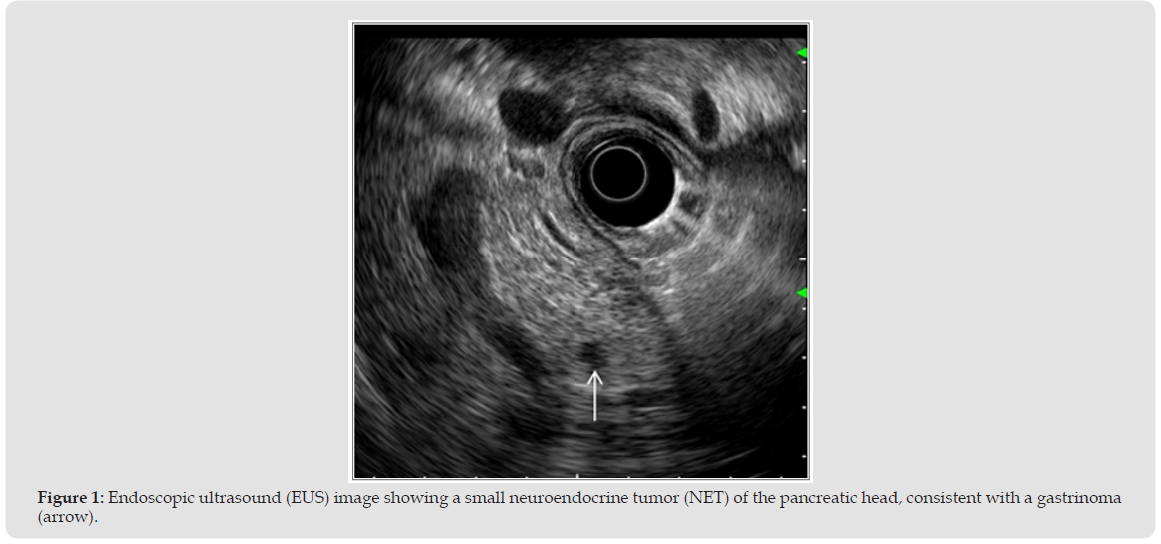

Since its introduction, EUS has provided unmatched resolution for gastrointestinal wall layers and peri-digestive structures. It rapidly became essential for staging esophageal and rectal cancer [1,2], with accuracy superior to CT and MRI for early T and N staging. The development of EUS-guided tissue acquisition (EUS-TA) allowed cytological and histological confirmation, transforming EUS into a diagnostic and therapeutic hub. Modern guidelines by the ASGE (2024) [3] and ESGE (2025) [4] have refined its role, recommending FNB needles for solid pancreatic lesions and recognizing EUS-BD as an evidence- based intervention after failed ERCP [9] (Figure 1).